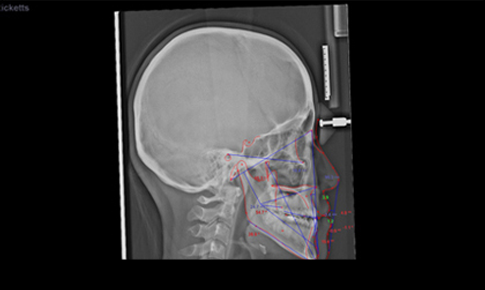

3차원 얼굴 스캔 및 촬영하기 때문에 인체에 무해하며 환자 얼굴 정, 측면의 X-ray와 사진을 종합하여 가상의 3차원적인 입체 영상을 만들고 분석과정을 통해 교정 적용의 변화된 얼굴 모습을 확인할 수 있어 정밀하고 예측 가능한 교정치료가 가능합니다.

디지털 카메라로 촬영한 사진에 비해 더 객관적이며 광대의 높이 차이나

콧대, 턱의 돌출 여부도 정확하게 확인하실 수 있습니다.